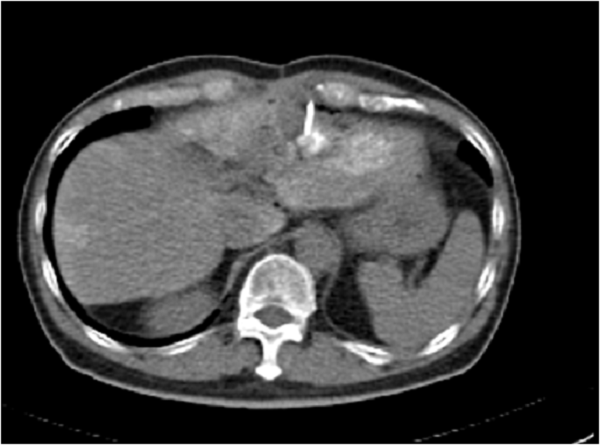

With better understanding of the disease pattern and the body’s requirements for liver function, various options for treatment of liver diseases and cancer must be available either as a single therapy or as a combination. Dr Chang is the Founding President of the Hepatopancreatobiliary Association of Singapore where in the early years of it formation, helped promote the integrated multi-disciplinary treatment of liver diseases. Such services available in GLAD Clinic and its associates include: Liver Transplantation Liver Resection Local ablative therapy (Radiofrequency, Microwave, Ethanol) TACE – Transarterial Chemoembolization Y90 Radioactive isotope embolization Systemic therapy e.g. Sorafenib